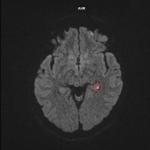

Tachycardie atriale focale

Un homme de 26 ans, militaire, consulte dans le cadre de sa visite de contrôle périodique d’aptitude au parachutisme...